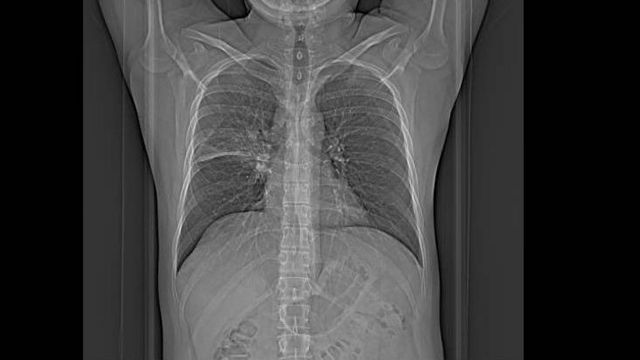

Exames de raio-x, tomografia e biópsia são utilizados para diagnosticar a doença

Fiz exame de escarro, raio-X, tomografia e broncoscopia. As imagens mostravam uma "mancha" em um canto do pulmão direito, mas ela não se parecia com uma tuberculose tradicional - por isso, os médicos suspeitavam até de fungos invasores.

A tuberculose só foi diagnosticada em uma biópsia: enfiam uma longa agulha do lado direito do tórax até o ponto do pulmão onde está a mancha. Um pedacinho é retirado para análise. A parte boa é que você dorme profundamente durante o exame.

Mancha no pulmão foi sinal de que algo estava errado